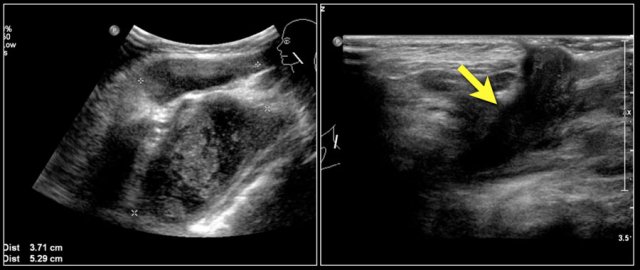

Here images of a six-month old boy with a vocal cord paralysis.

The MRI examination shows a mass between the parotid and submandibular gland (yellow arrow).

The signal characteristics are equal to the thymus (green arrow).

Ultrasound confirmed an ectopic thymic remnant (yellow arrow), with identical sonographic characteristics as the orthotopic thymus (green arrow).

Left: orthotopic thymus; right: ectopic thymus